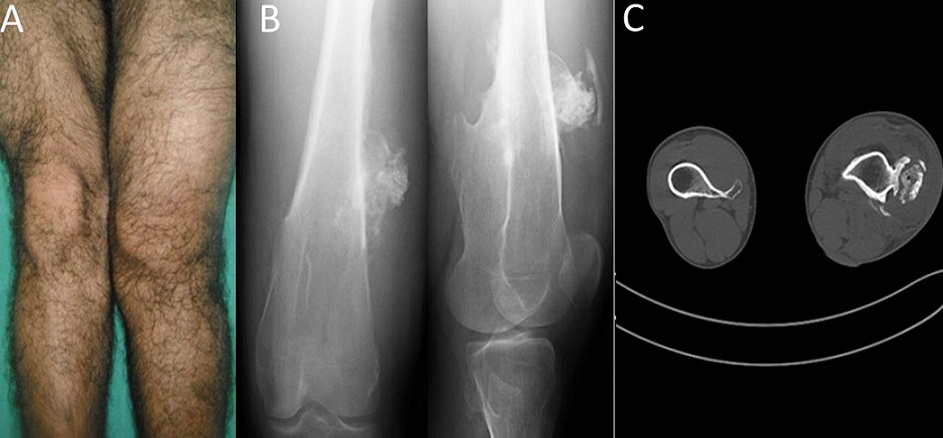

Bone tuberculosis simulating an exostosis

We report a diagnosis trap of bone tuberculosis of distal femur that simulates an exostosis. It was revealed by pain and swelling. Radiography and CT were in favor of exostosis. The histological study after surgical biopsy revealed caseating giant cell granulomas with epitheloid cells confirming the diagnosis. The outcome was favorable after antituberculous therapy. This study emphasizes the necessary awareness of pseudo-tumor appearance of tuberculosis in endemic area